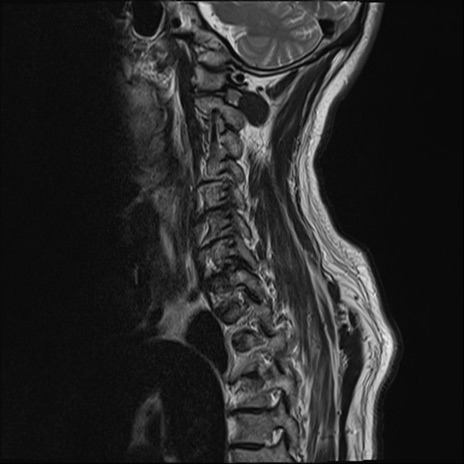

【整形】TIPS症例7 頚椎MRI T2WI(矢状断像)

頚椎MRI

T1WI(矢状断像)

矢状断像と横断像